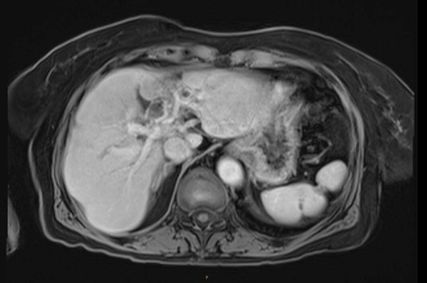

In der durchgeführten Staging-CT zeigte sich ein partielles Ansprechen (PR) mit Tumorgrößenreduktion von 49mm auf 33mm, die Lymphknoten blieben unverändert. Die Tumormarker sanken (AFP: 150, Ca19-9: 65). Aufgrund der persistierenden Diarrhö und des Verdachts auf einen Mischtumor erfolgte eine Umstellung der Therapie auf Cisplatin/Gemcitabin/Bevacizumab, wobei Gemcitabin ab Zyklus 2 wegen Fatigue auf 75% reduziert wurde und Cisplatin ab Zyklus 3 aufgrund von Ototoxizität abgesetzt werden musste. Nach vier Zyklen zeigte die MRT ein weiteres partielles Ansprechen (19×21mm), die Lymphknoten waren unverändert, die Tumormarker normalisierten sich erstmals.

Es erfolgte eine neuerliche Vorstellung im Tumorboard und es wurde die Entscheidung gefällt, eine Lokaltherapie durchzuführen. Im Juni 2021 erhielt die Patientin eine hypofraktionierte, extrakranielle stereotaktische Strahlentherapie (ED 12,5Gy, 3x, Zieldosis 37,5Gy auf die 65%-Isodose). Die Therapie wurde sehr gut vertragen. Im Verlauf zeigte sich ein anhaltendes komplettes Ansprechen (CR). Die Patientin befindet sich seither in regelmäßiger Nachsorge.

Im weiteren Verlauf traten rezente embolische, bihemisphärische Infarkte auf, ätiologisch als kardioembolisch bewertet. In der letzten MRT, viereinhalb Jahre nach Erstdiagnose, zeigten sich postradiogene Parenchymveränderungen, jedoch kein Hinweis auf ein Lokalrezidiv.